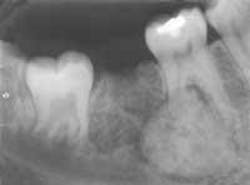

The patient's vital signs were all found to be within normal limits. Extraoral examination of the head and neck region revealed no enlarged or palpable lymph nodes. Intraoral examination revealed a slight bony enlargement of the buccal alveolar bone near the mandibular first molar. Based on this clinical finding, a periapical radiograph of the region was exposed. The film revealed a well-defined, round radiopacity surrounded by a radiolucent rim and obliterating the distal root of the mandibular first molar (see film). The patient was referred to an oral surgeon for biopsy and removal of the lesion.

The cementoblastoma has a fairly characteristic radiographic appearance. The lesion will appear as a well defined radiopaque mass attached to the root of a tooth. The opacity is surrounded by a thin, radiolucent rim. A term that is used to describe the radiographic appearance of a cementoblastoma is a "target" lesion; as the name suggests, the lesion resembles a target.

When viewed on a radiograph, the cementoblastoma typically surrounds the apex of the tooth and extends midway up to the root surface. The cementoblastoma may obliterate the involved root and cause extensive resorption.

In addition, the lesion often appears to be "blended" with the obliterated root surface, and it is difficult to identify where the lesion stops and the root surface begins.